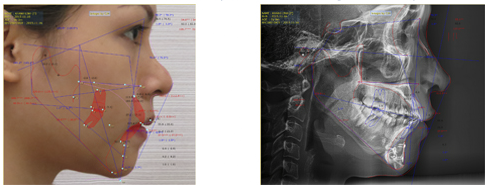

Phần mềm chuyên dụng phân tích hàm mặt Vceph của Mỹ

Phần mềm giúp phân tích chính xác cấu trúc xương hàm, xác định được hệ thống dây thần kinh cũng như vị trí cắt xương. Không sử dụng phần mềm này đồng nghĩa với việc bác sĩ chỉ “mổ mò" dựa vào cảm tính và ước lượng.

Bản phân tích của Emily Linh tại bệnh viện thẩm mỹ KIM trước khi tiến hành phẫu thuật. |

Máy X quang 3D conebeam CT, máy Pano Cepha

Máy sẽ giúp bác sĩ xác định, phân tích đặc điểm hình dáng xương hàm và độ xốp của xương, đồng thời xem xét những phần cần phải chỉnh sửa một cách chính xác nhất. Nếu không sử dụng các thiết bị này, bác sĩ không thể phân tích chính xác được cấu trúc xương hàm, dây thần kinh hàm dưới và vị trí cắt xương, dẫn tới các biến chứng nguy hiểm sau phẫu thuật gọt mặt V-line.